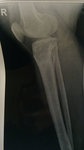

рентген в 90 дней.

Здравствуйте, Б.! Сращение идёт хорошо, но Вам ходить ещё месяц. в 120 дней ждём рентген.